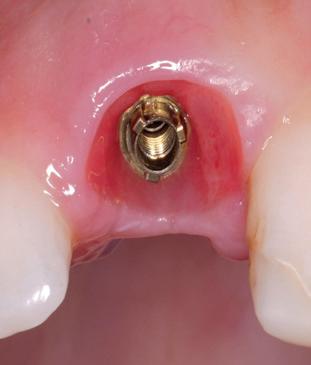

De implantaatplaatsing en de beslissende fout (afbeelding 1-13)

De extractie verliep voorspoedig, waarbij ik zoals al-

primaire stabiliteit van 60 Ncm.

11. Röntgenfoto ter controle van de plaatsing en de angulaire. Dit bone-level implantaat werd 4 mm onder de weke delen geplaatst.

12. Direct post-op. Een direct geplaatste tijdelijke kroon. Vastgezet met een torque van 20 Ncm en gehecht met prolene 5/0.

tijd probeerde de buccale botlamel intact te houden. Dit is cruciaal voor latere botbehoud en implantaatplaatsing. Na curettage en spoelen van de alveole beoordeelde ik de situatie opnieuw: de botcondities leken gunstig voor een immediaat implantaat.

Hier begon echter de cruciale fout in mijn klinisch besluitvormingsproces. In mijn streven naar maximale primaire stabiliteit - wetende dat immediaat belasten enkel mogelijk is bij hoge stabiliteit -on-

13. Röntgenfoto ter controle van de pasvorm van de direct geplaatste tijdelijke kroon.